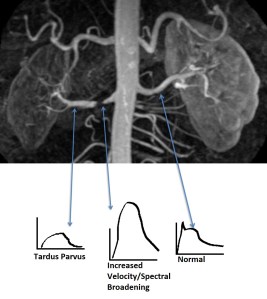

Renal Artery Doppler